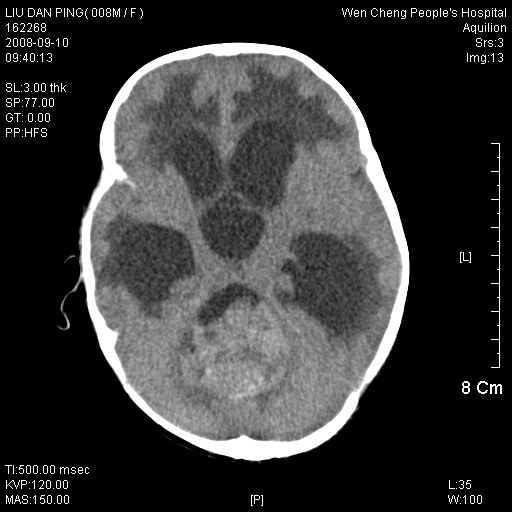

以下是引用深泽交通医院在2008-9-10 15:08:00的发言:[br]髓母瘤并脑积水

以下是引用卜一在2008-9-10 16:21:00的发言:[br]髓母细胞瘤伴梗阻性脑积水!支持![br]髓母细胞瘤特点:—般直径大于3.5cm,位于后颅凹中线之小脑蚓部。累及上蚓部的肿瘤延伸到小脑幕切迹之上,ct平扫肿瘤多呈均匀一致的高或等密度病灶,增强检查呈均匀一致的强化。病灶中有小坏死时,平扫亦可呈不均匀之混杂密度,注药后有增强。[br]

以下是引用yuhongjun在2008-9-10 16:57:00的发言:[br]髓母细胞瘤伴梗阻性脑积水.

以下是引用zjzjr在2008-9-10 15:09:00的发言:[br]髓母细胞瘤伴梗阻性脑积水.